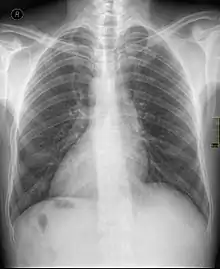

| Chest X ray of a person with dextrocardia situs inversus showing the cardiac apex pointing towards right | |

Dextrocardia (from Latin dextro, meaning "right hand side," and Greek kardia, meaning "heart") is a rare congenital condition in which the apex of the heart is located on the right side of the body, rather than the more typical placement towards the left.[1] There are two main types of dextrocardia: dextrocardia of embryonic arrest (also known as isolated dextrocardia) and dextrocardia situs inversus. Dextrocardia situs inversus is further divided.

Dextrocardia situs inversus refers to the heart being a mirror image situated on the right side. For all visceral organs to be mirrored, the correct term is dextrocardia situs inversus totalis.[4][5]